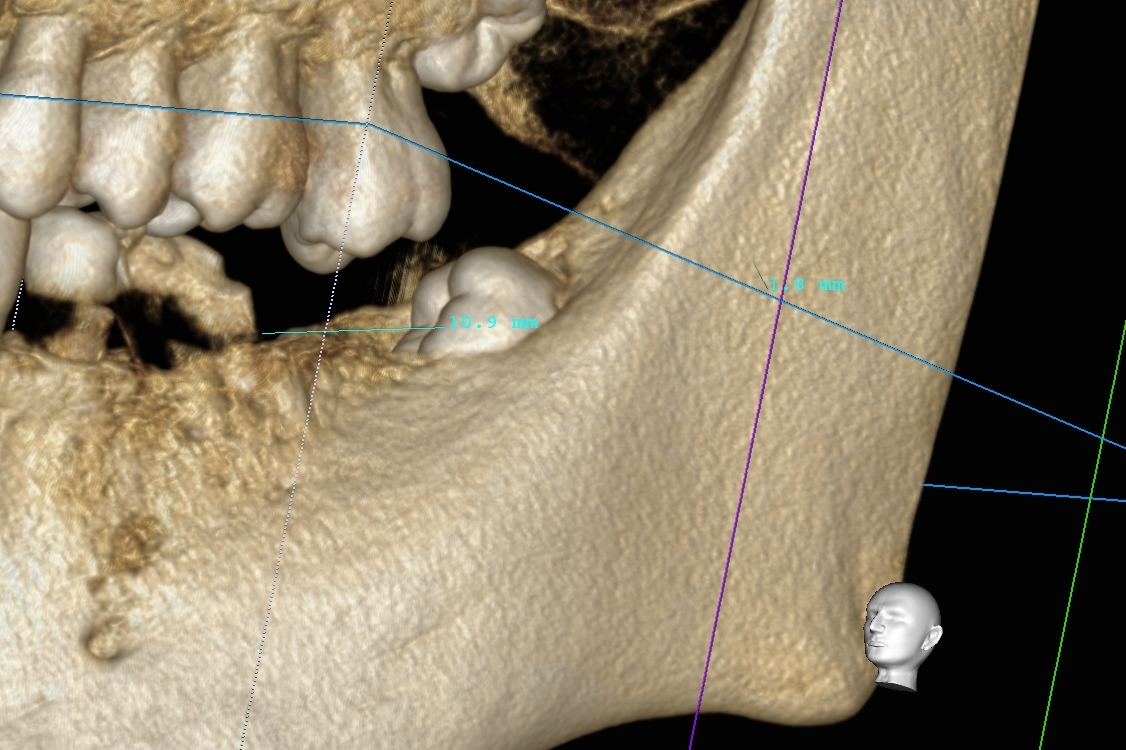

歯茎の下にほぼ全て埋まった親知らずの抜歯